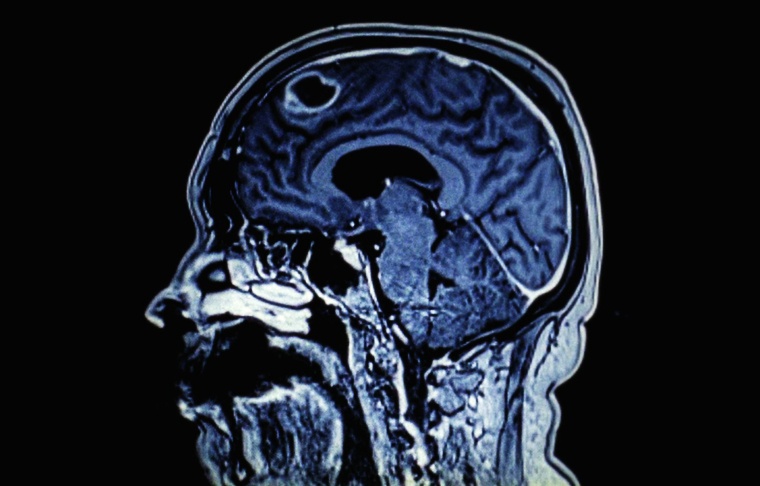

Dos jóvenes médicos, su médico jefe y tres pacientes nos llevan por la vida de un ala de oncología. Una mirada de cerca a la relación entre médicos y pacientes, y cómo cada uno de ellos se ocupa de la enfermedad y de la muerte cercana.